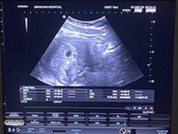

ของเราไปซาวด์ตอน7วีค ก็ยังไม่เจอจ้า ครั้งที่2หมอนัดอีกประมาณ1เดือน ส่องกล่องเจอจ้า

5wยังไม่เห็นหรอกคะเพราะน้องเล็กมากๆๆตอนเรา5wก็ซาวไม่เห็นน้องเหมือนกันคะเจอตอน8wคะ

บ้านนี้ซาวตอน7วีคเจอแต่ถุงตั้งครรภ์จ้า หมอนัดซาว11วีคอิกรอบจ้าหวังว่าคงเจอน้อง

ไม่ต้องกังวลนะคะเรา5วีคก็ไม่เจอค่ะ เจอตอน7วีคซาวผ่านช่องคลอดค่ะถึงเจอ🥰

ท้องยังอ่อนเกินไปค่ะ แม่บ้านนี้ก็เป็นพอ8wถึงได้เห็นตัวน้อง

อาจจะเจอแค่ถุงตั้งครรภ์ค่ะรอสักประมาณ9-10wค่ะจะเห็นน้องชัดมาก

นี่ 6w เจอเล็กๆ แต่หมอยังไม่ให้ฝากค่ะ ต้องรออีกเดือนค่อยไปฝาก

ของพี่ก็ไม่เจอค่ะไปตรวจตอน5w หมอนัดไปใหม่อีกรอบ

อายุครรภ์ยังน้อยค่ะ รอ8-10วีคไปซาวด์อีกทีนะคะ